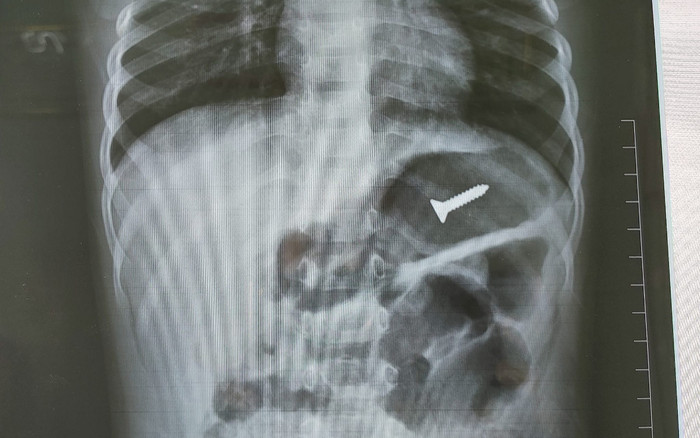

Kết quả chụp X-Quang cho thấy có 1 di vật cản quang trong ống tiêu hóa cao. (Ảnh: BVCC).

Ngay sau đó, người thân đã đưa trẻ đến Bệnh viện đa khoa tỉnh Tuyên Quang để thăm khám. Kết quả chụp X-Quang cho thấy có 1 di vật cản quang trong ống tiêu hóa cao, các cơ quan khác chưa phát hiện bất thường.